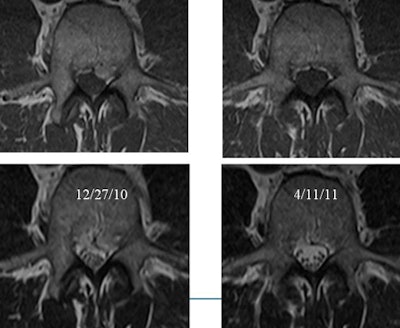

In their own study, Cleveland Clinic researchers followed for two years 246 patients who had a variety of functional pain issues. Sixty-four percent of those with back and leg pain had a herniation on imaging, and 57% of those with back pain had a herniation.

However, over six weeks there was complete resolution in 23% of those with herniation. Also, 13% of those with herniation developed a second herniation between the first and second studies (Radiology, November 2005, Vol. 237:2, pp. 597-604).

"There is no correlation between the number of herniations and how big they were and the patient's symptoms, and whether they were herniated didn't seem to correlate with how the patient did," Modic said.